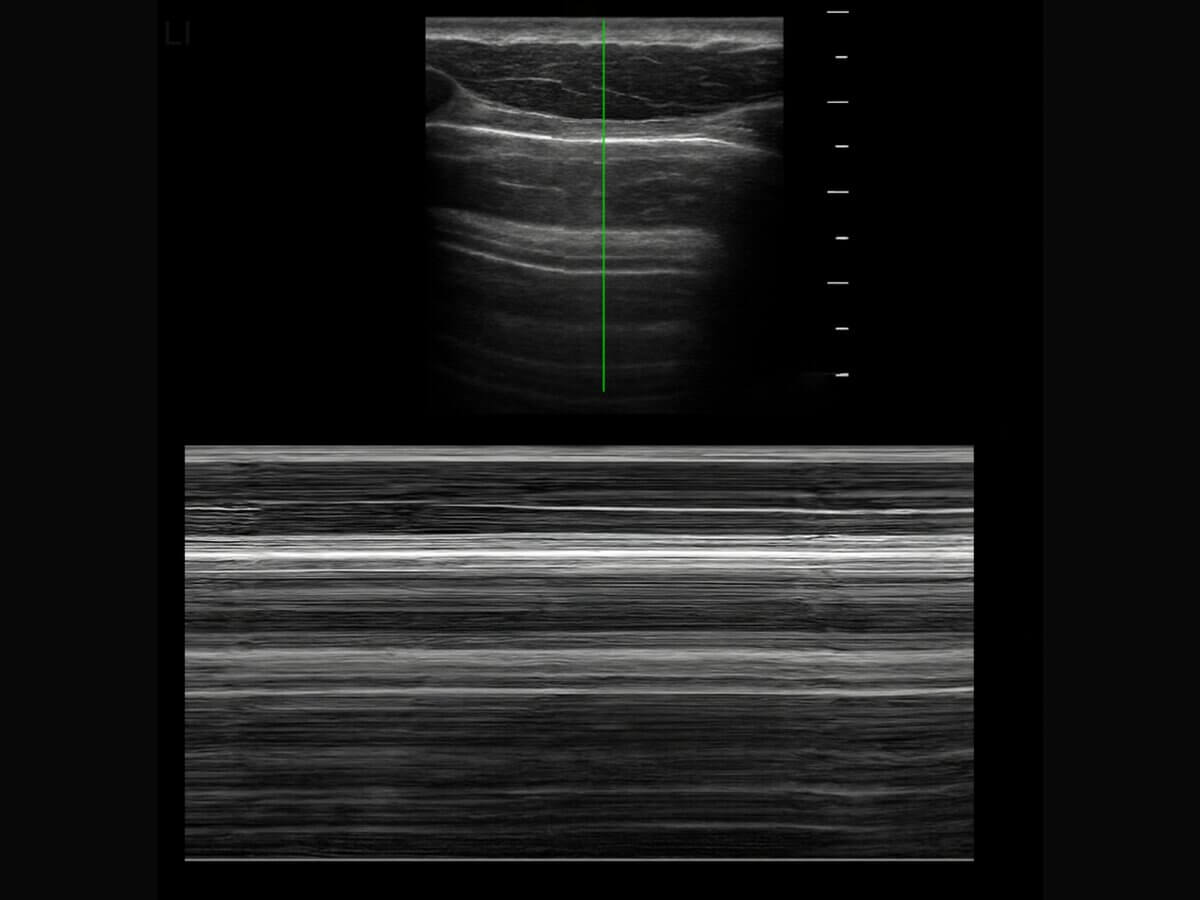

Das Barcode-Zeichen ist ein sonographisches Zeichen, das bei einem Pneumothorax im M-Mode des Lungenultraschalls sichtbar wird. Es ähnelt dem Bild eines Barcodes.

Liegt ein Pneumothorax vor, fehlt das Seashore-Zeichen. Im Ultraschall kann in diesem Fall kein Lungengleiten festgestellt werden und im M-Mode ist ausschließlich eine Reihe an parallel verlaufenden Linien zu erkennen, die an einen Barcode erinnern.

Im Lungenultraschall liegt physiologisch das sogenannte Seashore-Zeichen vor. Die Haut, das subkostale Fettgewebe, die Muskulatur und Pleura parietalis sind als unbewegliche, parallel verlaufende Linien erkennbar ("Wellen"). Die Pleura visceralis und die Lungen bewegen sich physiologischerweise minimal, sodass sie sich als Rauschen darstellen ("Sand"). Somit ergibt sich das Bild einer Meeresküste.